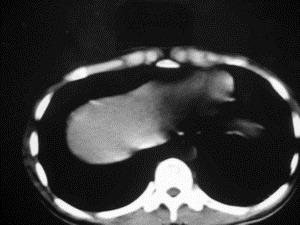

患者女,20岁,被车撞伤3小时,pe:全腹肌紧张,压痛反跳痛,以右上腹为著,肠鸣音减弱。有手术结果。![]() ![]() ![]() ![]() ![]() ![]() ![]() ![]() ![]() ![]() ![]() ![]() ![]() ![]() ![]() ![]() ![]() ![]() ![]() ![]() ![]() jiajie发言: ![]() 考虑空腔脏器穿孔。 dyqct发言:考虑:1、肝左叶外侧段断裂伤伴少量腹血。2、空腔脏器穿孔。 fangzheng发言:仅见腹腔内游离气体,提示空腔脏器穿孔。 guoke发言:胃内密度增高,肠腔内充满气体,考虑肠腔破裂出血 mmg94发言:胃后壁见一增厚软组织密度影,肝左叶前见游离气体影,左腹腔内局部肠管壁、系膜增厚。并见类圆形软组织。以上征象提示消化道管腔破裂,小肠、肠系膜挫裂伤,腹腔血肿形成。 拾荒者发言:肝实质密度不均匀,胃内见不均匀高密度影。考虑:肝挫裂伤,胃内应激性溃疡出血。 守望可可西里发言: 以下是引用jiajie在2006-6-20 15:49:00的发言:[br] [br][br]考虑空腔脏器穿孔。jiajie老师,我鼓起了很大的勇气才决定给您唱个反调儿,如果我错了,请您一定给我指出来,谢谢您了。我反复看了解剖图谱,觉得您所说的“考虑空腔脏器穿孔”上图所用箭头标明的不是游离气体。请您看以下几幅图片: ![]() ![]() ![]() ![]() ![]() ![]() ![]() ![]() 再请您看向医生老师发表的解剖图谱3幅 ![]() ![]() ![]() 这以下几幅图,我认为是肝包膜下积血。不过,说实在话,我没有发现有明显的肝挫裂伤。不对的地方请您一定指出来,再次感谢您了,jiajie 老师! ![]() ![]() ![]() ![]() 这下面几幅图片,我认为有明显的左中上腹部小肠损伤。 ![]() ![]() ![]() ![]() ![]() ![]() ![]() ![]() jiajie 老师,估计我说的是错误的,但我实在闹不明白,请您一定不要笑话我,并指出我的错误,以便于我减少工作中的失误。再次感谢您了,jiajie 老师! 至于胃内的不均匀高密度,我认为拾荒者战友说的有道理,胃内应激性溃疡出血和胃内容物混合所致。 手术结果:左肝叶(iv段)前缘长约8cm挫裂伤口,舌叶根部下< |